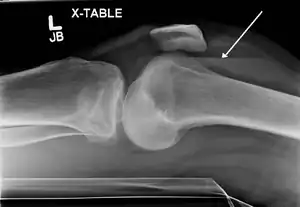

Lipohemarthrosis (presence of fat and blood from bone marrow in the joint space after an intraarticular fracture) seen on X-ray in a person with a subtle tibial plateau fracture -

Lipohemarthrosis due to a tibial plateau fracture -